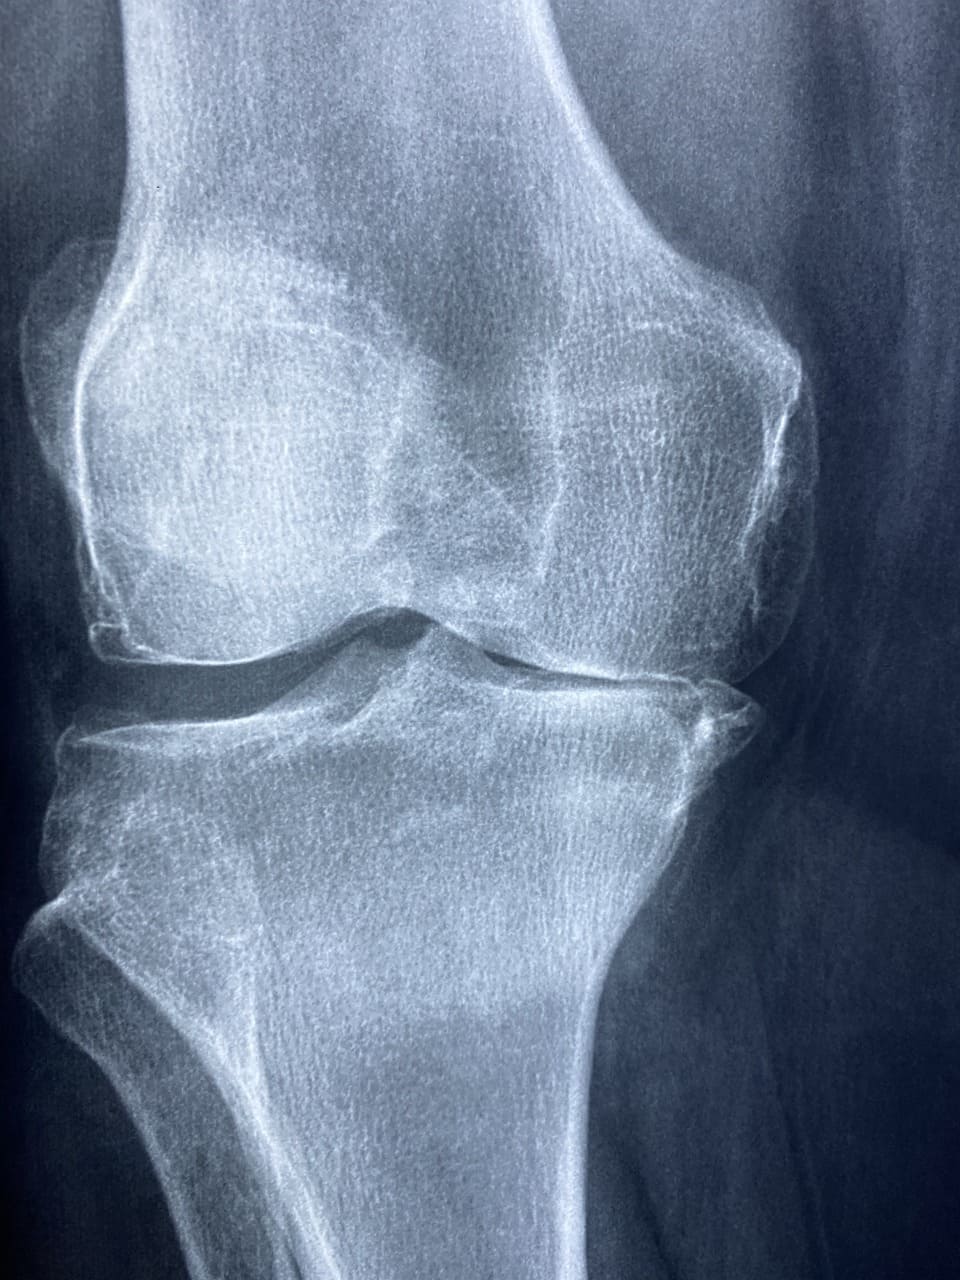

무릎 연골연화증을 진단하기 위해서는 여러 가지 검사와 진단 방법이 필요합니다. 첫 번째로, 의사는 환자의 증상과 병력을 확인하고 무릎을 시진과 촉진하여 통증의 위치와 심각성을 평가합니다. 이러한 기본적인 검사를 통해 의심되는 연골 손상 부위를 파악할 수 있습니다. 두 번째로, 영상 검사가 필요합니다. 엑스레이는 무릎 뼈의 상태를 확인하는 데 유용하지만, 연골은 엑스레이에서 잘 보이지 않습니다. 따라서 MRI(자기 공명 영상) 검사가 가장 정확한 진단 방법으로 사용됩니다. MRI를 통해 연골의 상태와 손상의 정도를 상세하게 확인할 수 있습니다.

| 엑스레이 | 무릎 뼈 상태 확인 |